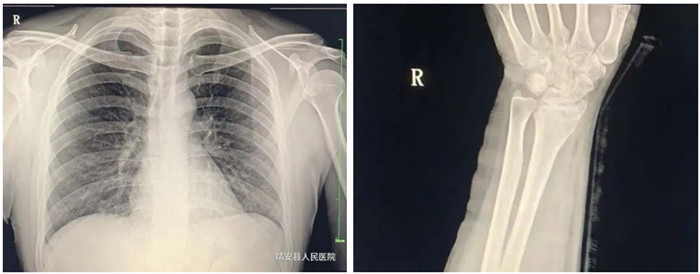

2.脊柱、四肢骨骼及關(guān)節(jié)

適應(yīng)癥:骨齡檢查、先天性發(fā)育異常、骨缺血性壞死;骨質(zhì)疏松、骨髓炎、骨腫瘤、骨關(guān)節(jié)創(chuàng)傷、骨關(guān)節(jié)結(jié)核、骨關(guān)節(jié)炎性病變、軟組織病變等疾病。

3.胸部

適應(yīng)癥:氣管支氣管病(支氣管結(jié)石及異物等);肺部病變(先天性發(fā)育異常、炎癥、結(jié)核、腫瘤等);縱膈病變(氣腫、血腫、腫瘤與囊腫等)。